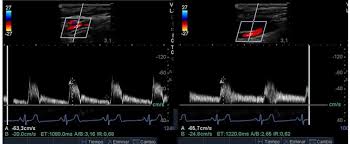

Pruebas complementarias. Eco-Doppler: se observa velocidad claramente disminuida en comparación con la contralateral a nivel poplíteo y pedio. Sospecha de trombosis paraneoplásica.

Hallazgos ecográficos

El uso de ecografía en atención primaria y urgencias puede ser muy útil para ayudarnos en el diagnóstico como para confirmar nuestra sospecha inicial. En este caso nos confirmó claramente una isquemia arterial, enviando el paciente sin perder tiempo directamente a un hospital de tercer nivel, donde se completó el estudio y se procedió a escoger la técnica más apropiada para nuestro paciente concreto. Nuestra sospecha inicial se confirmó posteriormente a pesar de nuestras posibles dudas y lo errático de la clínica y las evaluaciones previas.